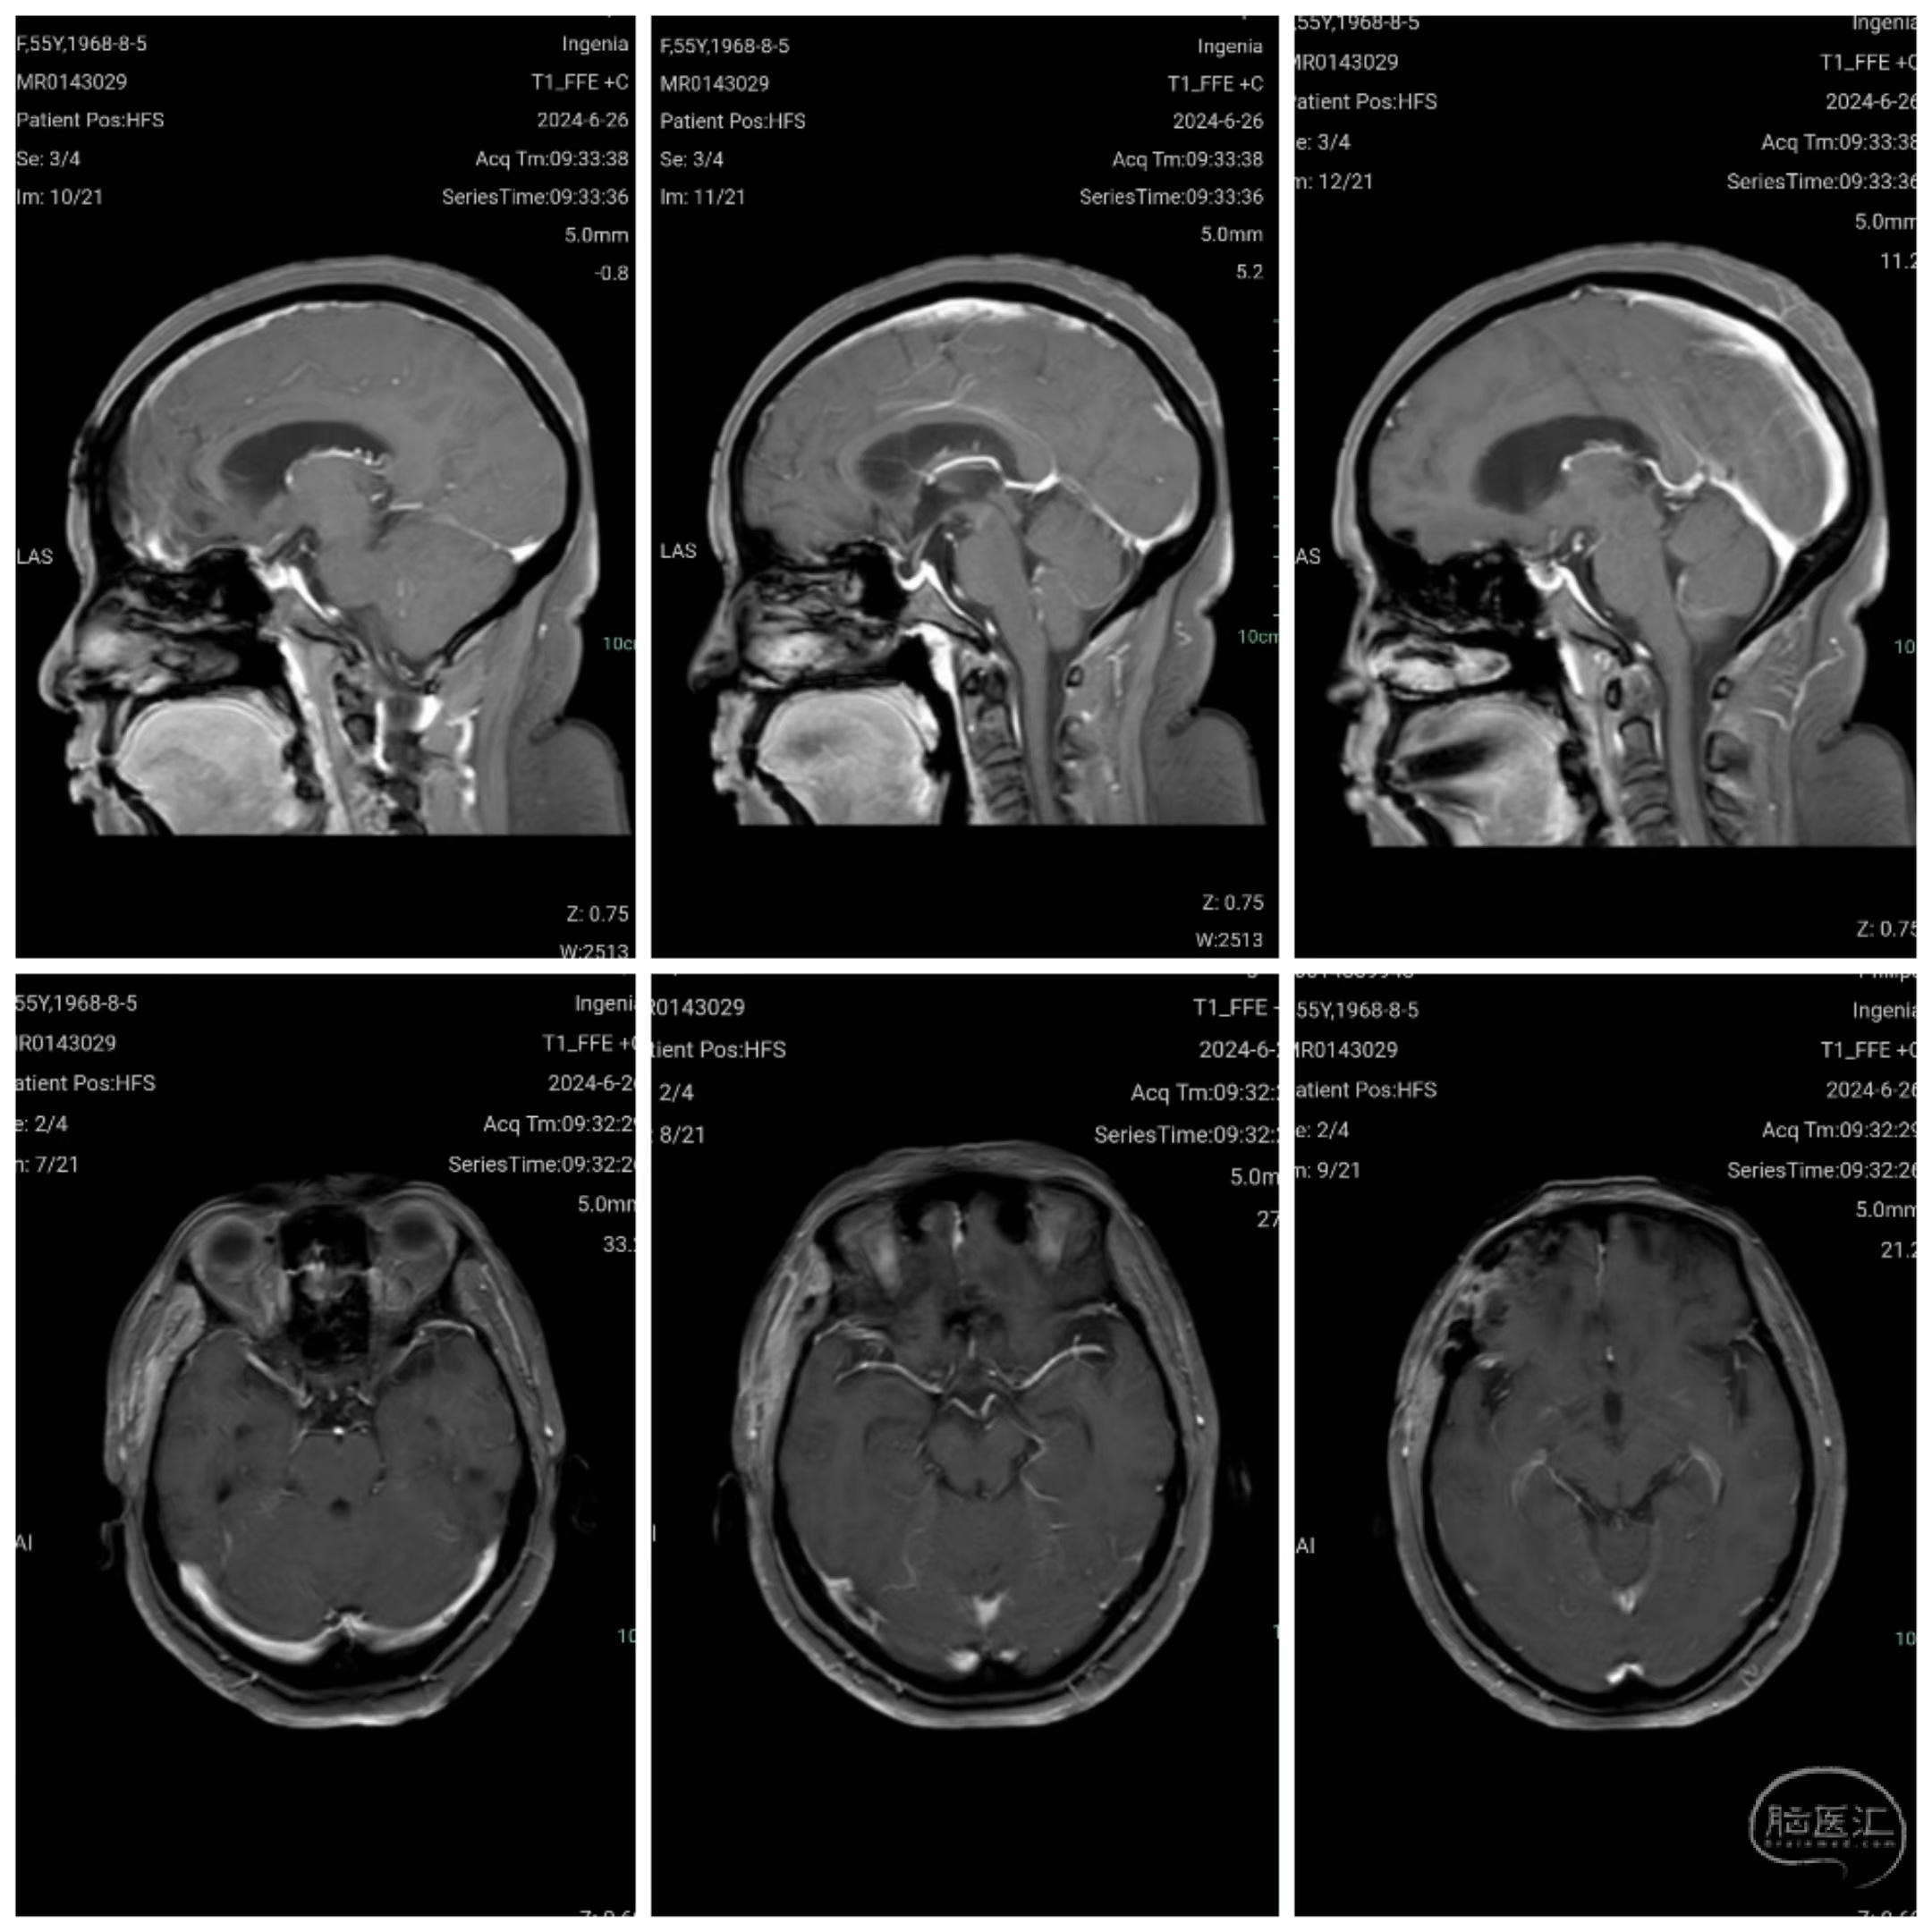

颅脑磁共振增强扫描示前颅底巨大脑膜瘤,基底前至鸡冠,后达垂体窝,基底宽。

手术前与手术后第十天后颅脑增强磁共振比较:前颅底巨大脑膜瘤影像学切除完全。

术后三个月颅脑强化磁共振显示肿瘤无明显残留。